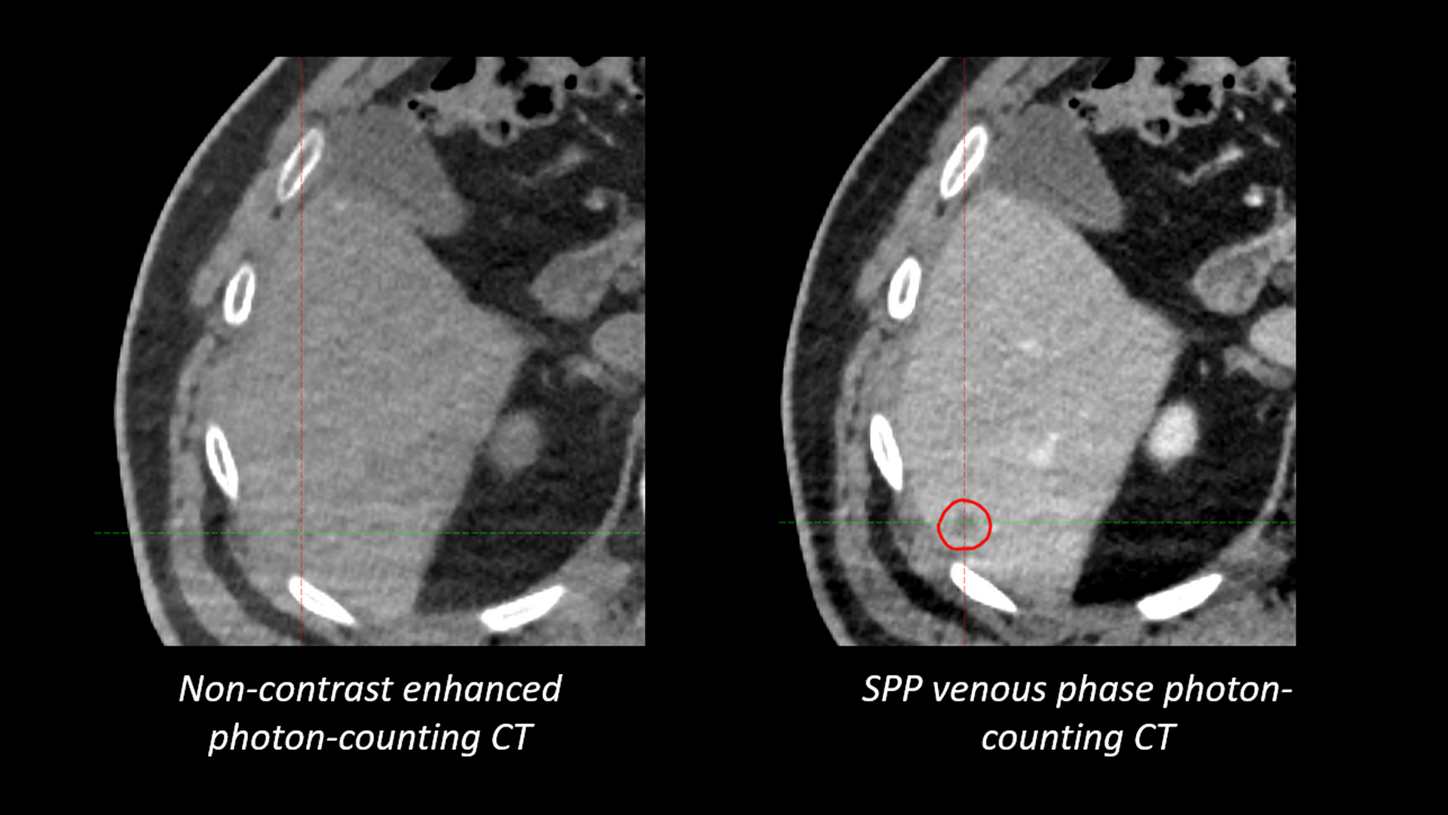

"Compared to previous images, those acquired with our new photon-counting scanner show considerably greater detail. For instance, we can now detect very small liver lesions as small as 4 mm on post-contrast images. The enhanced visibility provided by photon-counting technology enables us to use much narrower margins between the GTV and CTV, allowing for dose escalation鈥攎ight lead to improved patient outcomes." 9